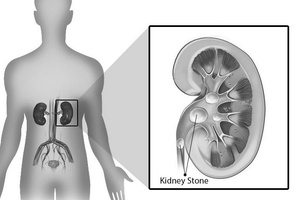

Камни, состоящие из оксалата кальция, в совокупности с компонентами фосфата кальция или без них составляют примерно 75 % от всех камней мочевыводящих путей.

Камни, состоящие из оксалата кальция, могут привлечь внимание врача в связи с тем, что они вызывают боли или гематурию. Эти симптомы обычно являются следствием острой обструкции, например при прохождении камня по мочеточнику. В некоторых случаях бессимптомный кальциевый камень можно обнаружить случайно, при радиографическом обследовании по поводу другого патологического состояния органов брюшной полости или костно-мышечного аппарата. Радиографическое обследование при асимптоматических камнях также может быть назначено после выявления микрогематурии или пиурии, при обычном анализе мочи.

На обзорной урограмме камни, состоящие из оксалата кальция, определяются в виде контрастных теней, их плотность примерно соответствует таковой у йодсодержащего контрастного вещества. Таким образом, после введения контрастного препарата во время урографии или ретроградного исследования камень может не определяться. Ультразвуковое исследование и компьютерная томография позволяют выявить такие камни, однако этими методами невозможно отдифференцировать камни, состоящие из оксалата кальция, от камней другого состава .